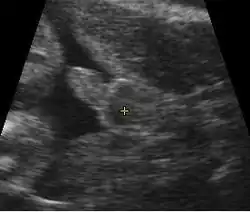

Imagem colorida artificialmente, mostrando saco gestacional, saco vitelino e embrião (medindo 3 mm entre os sinais +) -